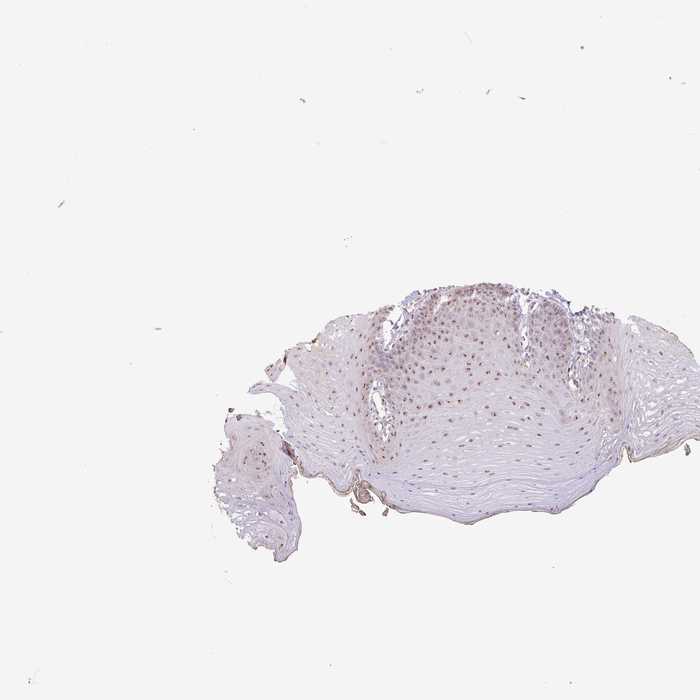

TISSUE PRIMARY DATA ORAL MUCOSA Show tissue menu

ORAL MUCOSA - Antibody stainingi

Antibody staining in the annotated cell types in the current human tissue is reported as not detected, low, medium, or high, based on conventional immunohistochemistry profiling in selected tissues. This score is based on the combination of the staining intensity and fraction of stained cells.

Each image is clickable and will lead to virtual microscopy that enables deeper exploration of all samples and also displays staining intensity scores, fraction scores and subcellular localization as well as patient and tissue information for each sample.

Antibody HPA053035

Squamous epithelial cells Medium